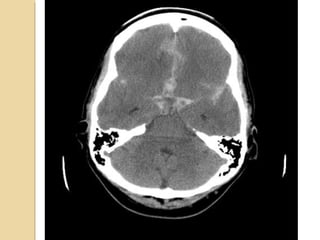

Subarachnoid hemorrageSubarachnoid hemorrage Canoriginate from direct vessel injury, contused cortex or intraventricular hemorrhage. Look in the interpeduncular cistern and Sylvian fissure Usually focal (but diffuse from aneurysm) Can lead to communicating hydrocephalus

Subarachnoid hemorrageSubarachnoid hemorrage

Can originate from direct vessel injury,

contused cortex or intraventricular

hemorrhage.

Look in the interpeduncular cistern and

Sylvian fissure

Usually focal (but diffuse from aneurysm)

Can lead to communicating hydrocephalus